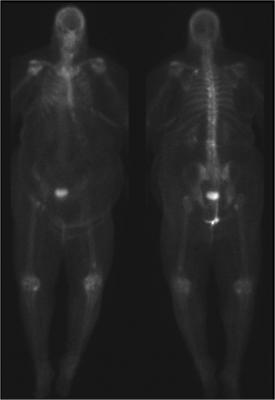

Additionally in an in vivo animal study, arthritis was induced in mice and was followed with intravenous injection of Manocept-Cy3 and epi-fluorescent imaging. Imaging results indicated that Manocept can be detected in inflamed joints in an in vivo animal model of RA.